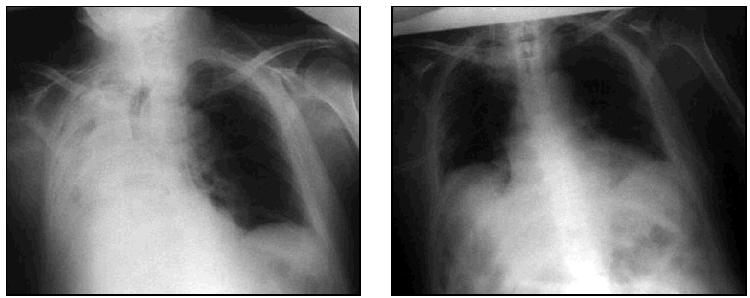

Diagnóstico

Se basa en la historia clínica y estudios como:

– Radiografía de tórax, que muestra infiltrados en zonas dependientes de la gravedad.